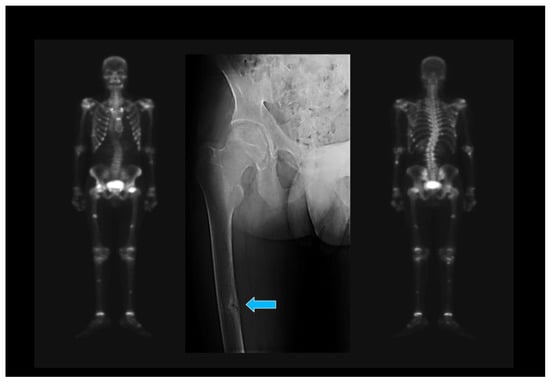

5.3. Oncogenic Osteomalacia

- Gupta, A.; Kandasamy, D.; Sharma, R.; Damle, N.; Goyal, A.; Goyal, A.; Agarwal, S.; Dharmashaktu, Y. Imaging characteristics of phosphaturic mesenchymal tumors. Acta Radiol. 2023, 2841851231160086. [Google Scholar] [CrossRef]

- Minisola, S.; Peacock, M.; Fukumoto, S.; Cipriani, C.; Pepe, J.; Tella, S.H.; Collins, M.T. Tumour-induced osteomalacia. Nat. Rev. Dis. Prim. 2017, 3, 17044. [Google Scholar] [CrossRef]

- Feng, J.; Jiang, Y.; Wang, O.; Li, M.; Xing, X.; Huo, L.; Li, F.; Yu, W.; Zhong, D.R.; Jin, J.; et al. The diagnostic dilemma of tumor induced osteomalacia: A retrospective analysis of 144 cases. Endocr. J. 2017, 64, 675–683. [Google Scholar] [CrossRef] [PubMed]